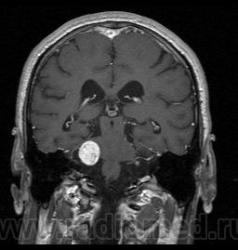

Пациент 35 лет, направлен неврологом из поликлиники с Ds: Рассеянный склероз? У данного пациента в течении года отмечается сильное головокружение и шаткость в походке, пришел на исследование на плечах у родственников. Данное исследование закачено на Dicom-сервер http: //www.radiomed.ru:8080/oviyam/oviyam? (под названием Brain-20101118).

Невринома правого слухового нерва

Если быть точным, VIII нерва;)

Более вероятнее невринома правого слухового нерва.